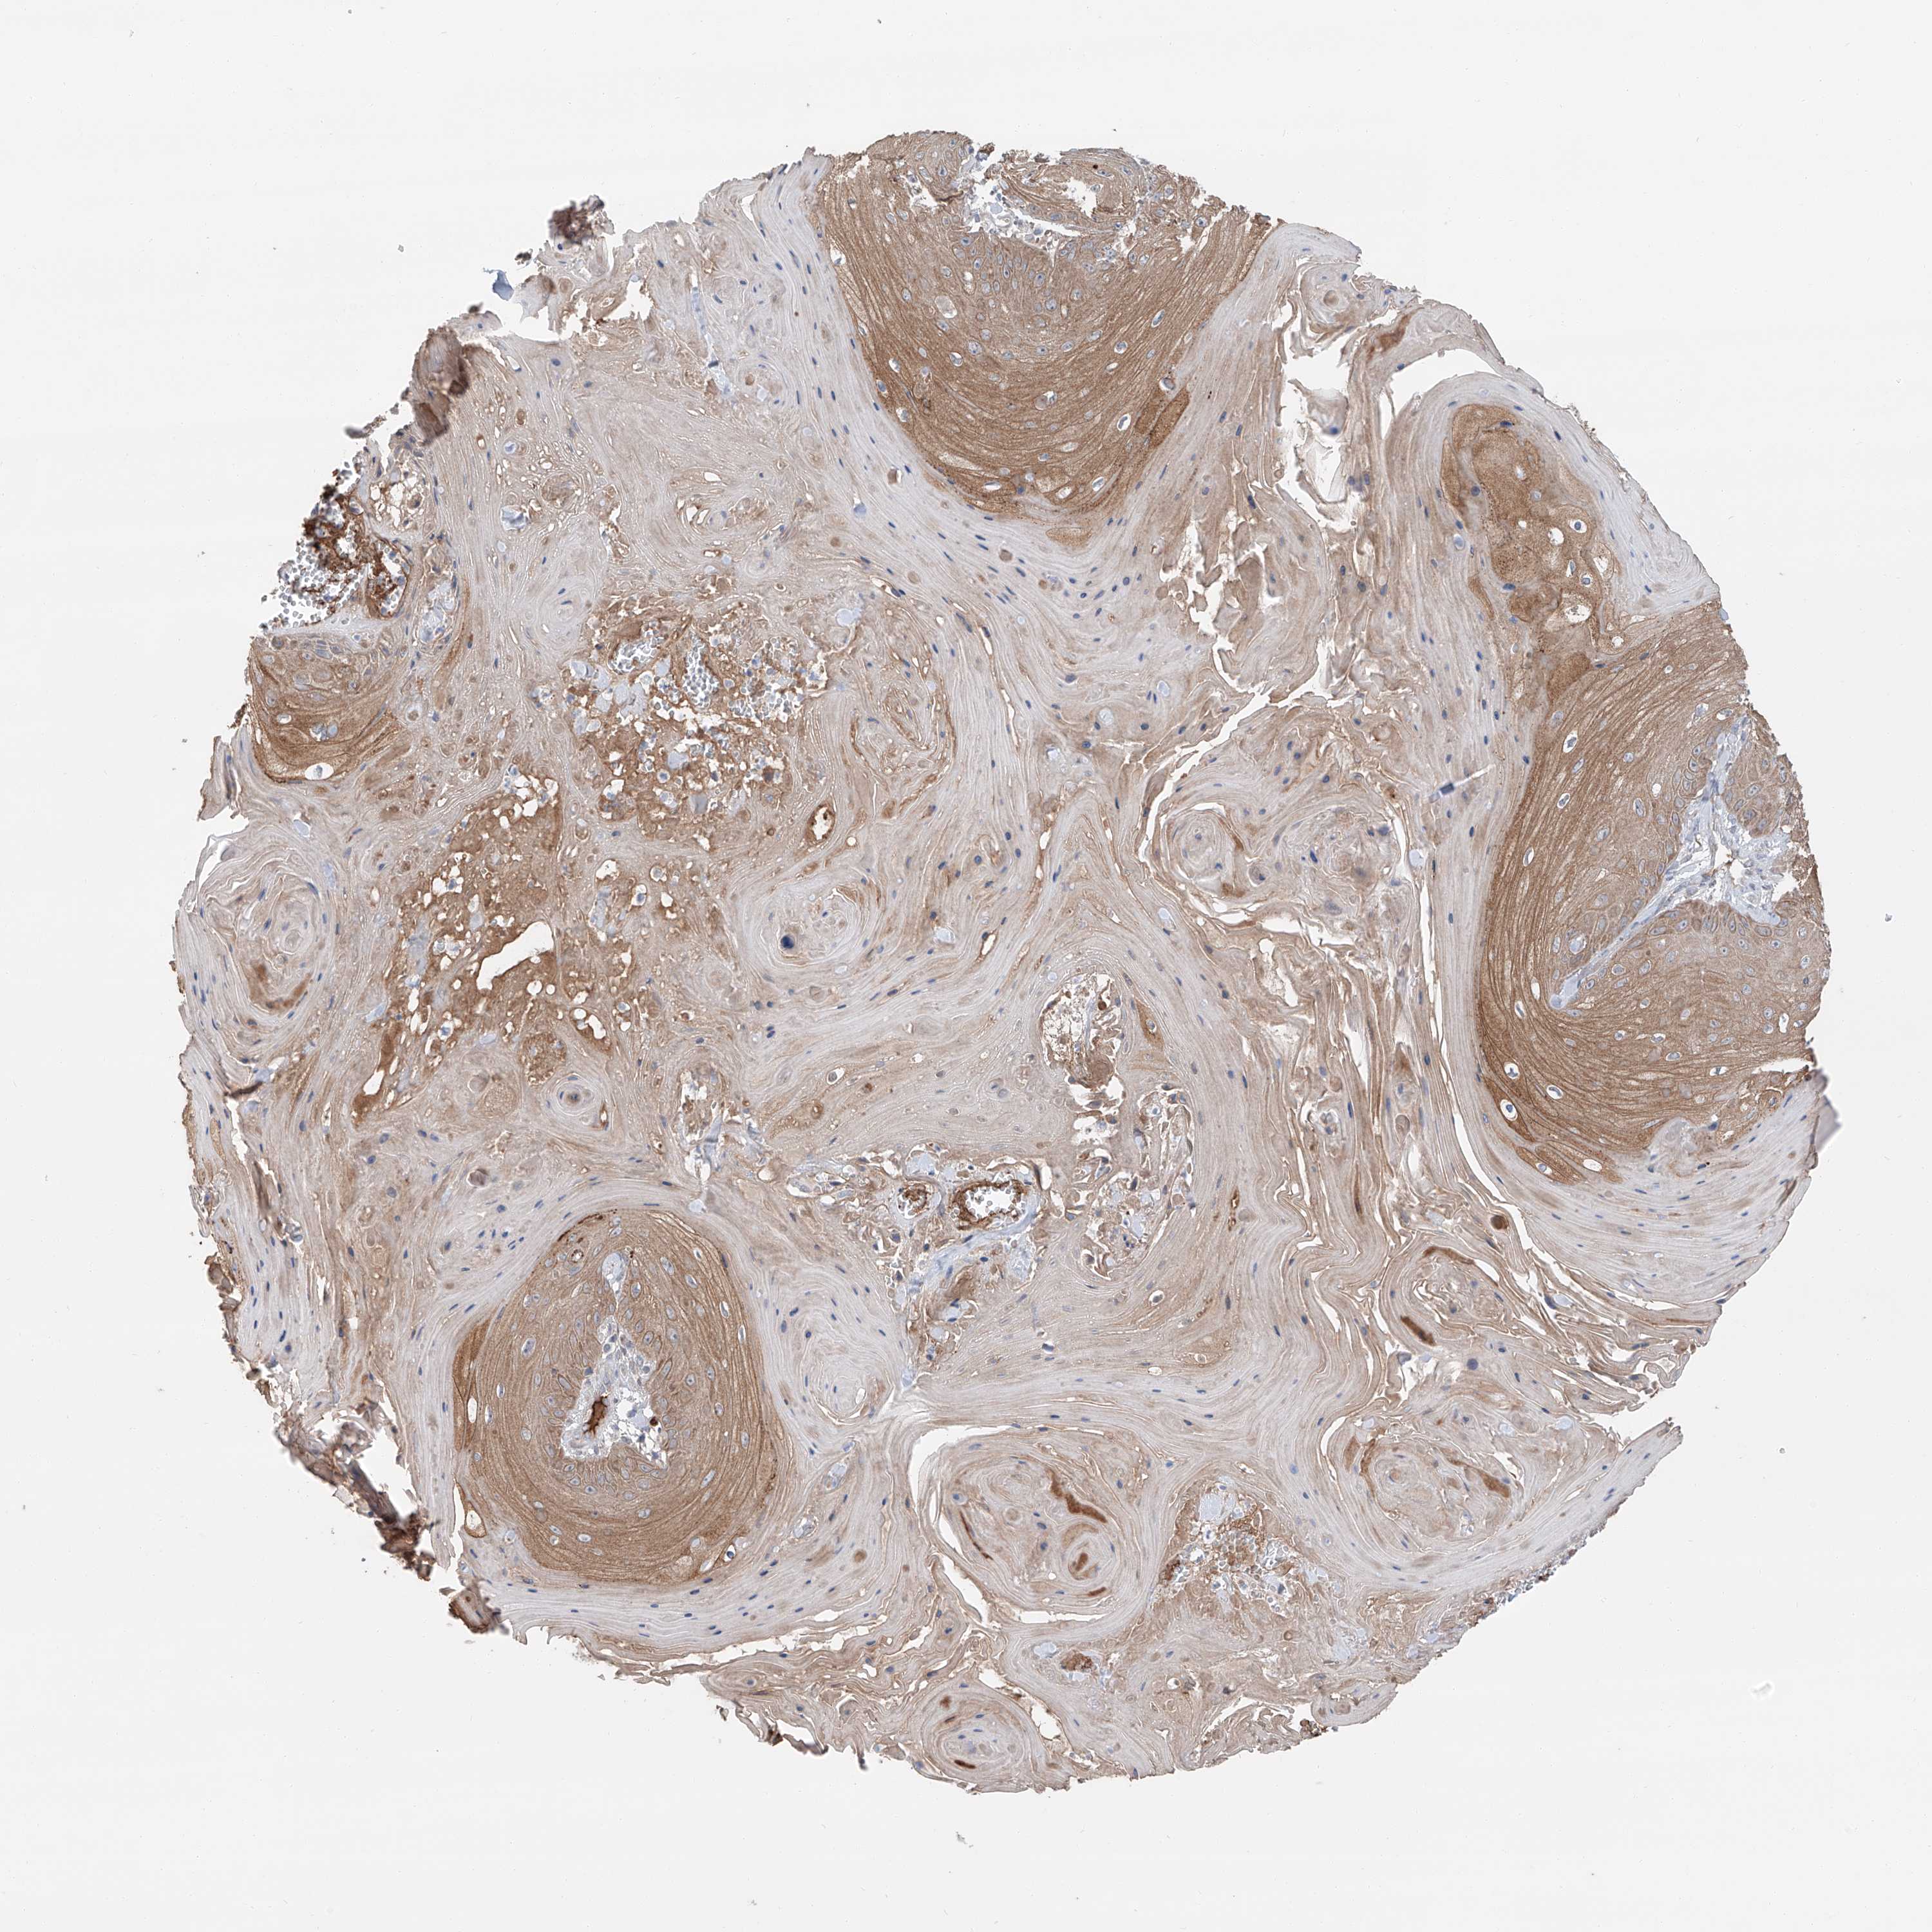

Basal cell and squamous cell cancer

SKIN CANCER - Protein expressioni

A mouse-over function shows sample information and annotation data. Click on an image to view it in a full screen mode. Samples can be filtered based on level of antibody staining by selecting one or several of the following categories: high, medium, low and not detected. The assay and annotation is described here.

Antibody stainingi

Antibody staining in the annotated cell types in the current human tissue is reported as not detected, low, medium, or high, based on conventional immunohistochemistry profiling in selected tissues. This score is based on the combination of the staining intensity and fraction of stained cells.

Each image is clickable and will lead to virtual microscopy that enables deeper exploration of all samples and also displays staining intensity scores, fraction scores and subcellular localization as well as patient and tissue information for each sample.

Antibody HPA031794

Staining

High

Medium

Low

Not detected

Intensity

Strong

Moderate

Weak

Negative

Quantity

>75%

75%-25%

<25%

None

Location

Nuclear

Cytoplasmic/membranous

Cytoplasmic/membranous,nuclear

Basal cell carcinoma

Squamous cell carcinoma, NOS

Squamous cell carcinoma, metastatic, NOS